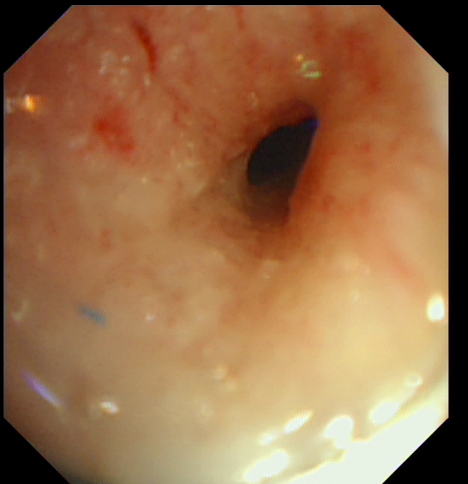

支架植入术后气管通畅